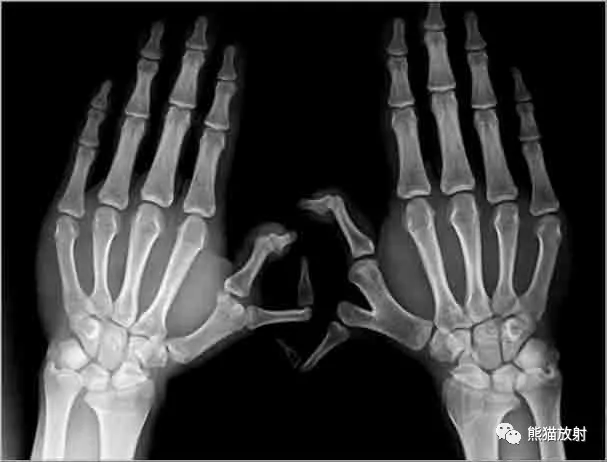

正常手臂骨头x光图片

正常手臂骨头x光图片,正常的肘关节x光图

正常人的手骨x光图片

正常手骨拍片图片

正常手骨x光图

手掌x光图片